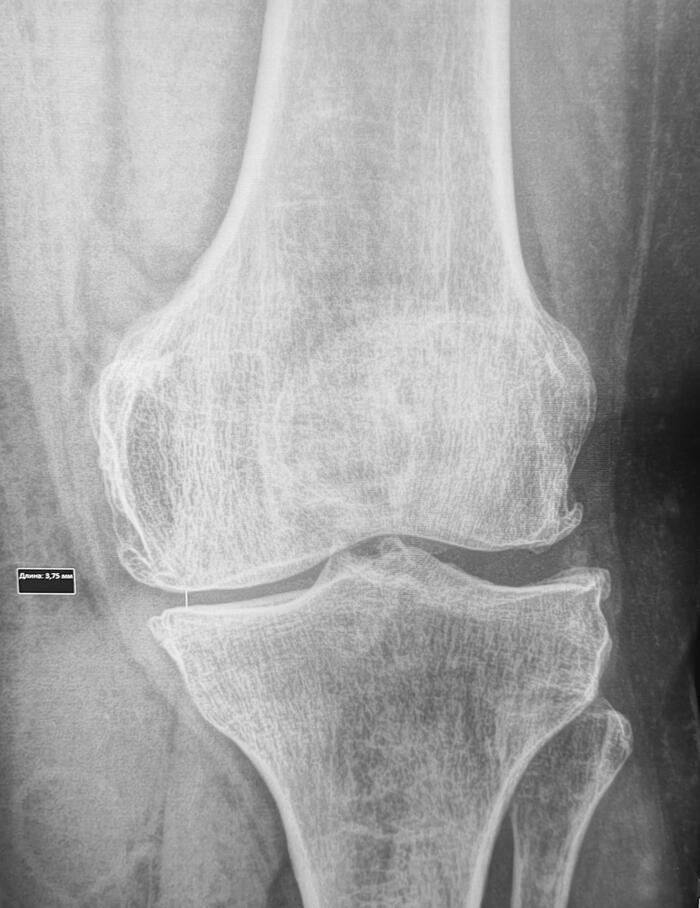

Стресс-перелом мыщелка большеберцовой кости

Стресс-перелом – это трещина в кости, вызванная повторяющимися нагрузками, а не единичным травматическим воздействием.

Косая линия просветления костной ткани в медиальном мыщелке левой б/б кости, сужение рентгенологической щели левого коленного сустава в медиальных отделах до 3.7,краевые остеофиты, субхондральный склероз суставной поверхности, заострение, деформация межмыщелковых возвышений. Заключение: Стресс-перелом медиального мыщелка левой большеберцовой. Гонартроз слева 2 ст.

Категория годности по ст.85(Временные функциональные расстройства костно-мышечной системы, соединительной ткани, кожи и подкожной клетчатки после лечения болезней, ранений, травм, отравлений и других воздействий внешних факторов) Г-временно не годен к военной службе сроком на 3 мес., с последующим оформление с диагнозом гонартроз 2 ст. по ст.65в-В(ограниченно годен к в/сл).